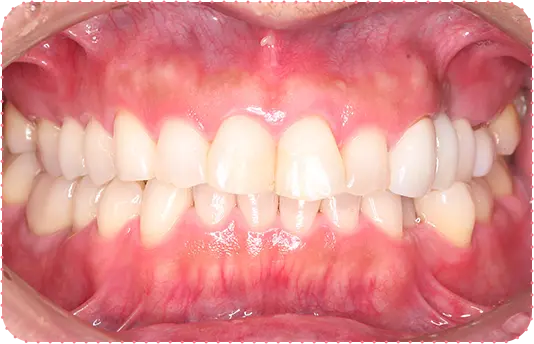

主訴

前歯をインプラントにしてほしい

治療期間

8か月

治療費

約150万円

治療内容

右上1番と左上1番をインプラント、右上2番をラミネートべニア、左上2番をセラミッククラウンにて修復

治療のリスク

治療後に口腔内管理が不適切な場合、埋入したインプラントが感染・炎症を起こす可能性があります。

しみたり、違和感が生じることがあります。咬み合わせによっては、セラミックが欠ける可能性があります。